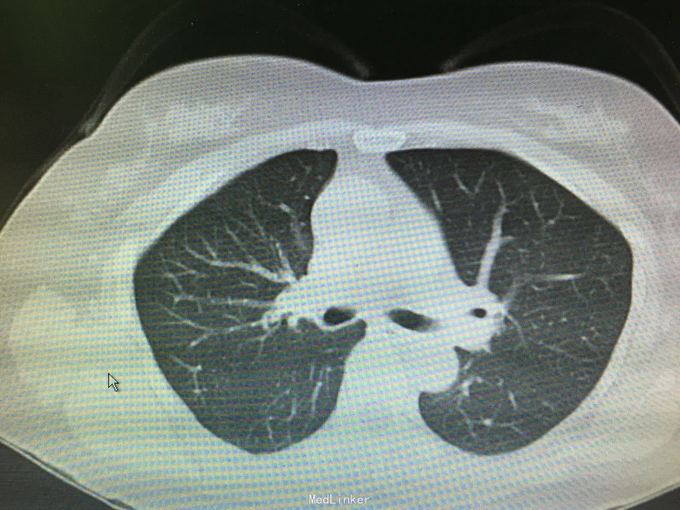

查体:无殊,无阳性体征。 辅助检查:CTU:左肾萎缩,考虑肾结核自截肾。 胸部CT 右肺少量纤维化灶伴局部胸膜粘连改变。